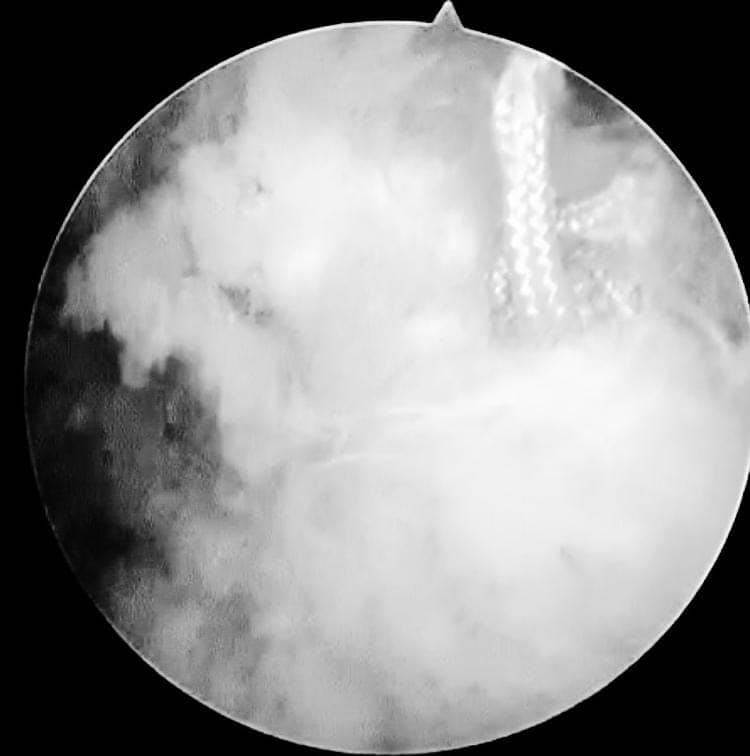

مشيرًا الى أن ذلك النوع من الكسور يكون قريبًا جدًا من الأعصاب والأوعية الدموية الرئيسية للساق والتي توجد خلف مفصل الركبة.. حيث تم الوصول الى الكسر وإعادة بناء سطح المفصل وتثبيته باستخدام شريحة ومسامير وأسلاك معدنية باستخدام جرح ٧ سنتيمترات خلف الركبة واستخدام مسامير جانبية مجوفة بدون فتح لتثبيت الجزء الخارجى من سطح المفصل، وتم الاطمئنان على الأوعية الدموية قبل إفاقة المريض، وبعد تمام الإفاقة.. تم الاطمئنان على الأعصاب والأوعية للمريض.

وأضاف أنه نظرًا لقرب هذا الكسر من سطح المفصل تم عمل أشعة مقطعية بعد الجراحة للتأكد من جودة بناء المفصل وعدم وجود أى بروز للمسامير داخل المفصل، وجارٍ تحضير المريض لعمل رنين مغناطيسى لتحديد الأربطة الداخلية والخارجية للركبة التي ستحتاج لإعادة بناء بالمنظار.